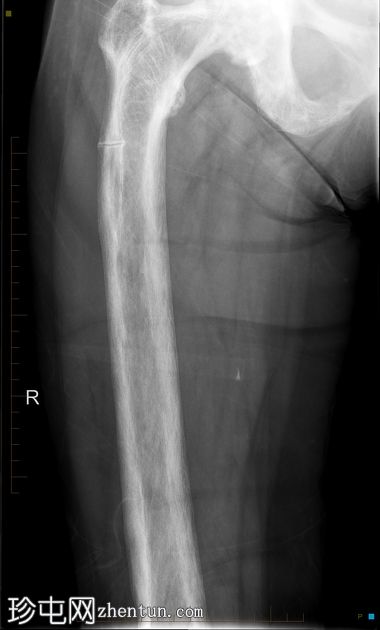

患者因跌倒后出现右髋

。

年龄:80岁

性别:女

X线片

正位片

显示右侧股骨近端香蕉状骨折,伴右侧股骨和髋臼广泛性佩吉特病。

本病例展示了右侧髋关节和股骨广泛性佩吉特病继发的香蕉状骨折的典型特征,经右侧骨盆和髋关节X线及CT检查证实。